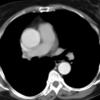

Ao Diss 1c

Date: 01/21/2006

Views: 3700